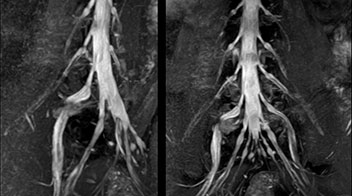

According to Tanji, methods such as ProSet FFE, STIR or 3D VISTA are anatomically nonselective because background signals, for instance from blood vessels, often interfere with nerves, which hampers evaluation of details, especially at the peripheral side of the nerves.

“For both brachial and lumbar plexus, we are currently using a 230 mm FOV and voxels of about 1 x 1 x 2 mm acquired (1 x 1 x 1 mm reconstructed). This provides us a good representation of the nerves, even though this FOV is relatively small. Regarding the inplane resolution, we hope to be able to bring that down to 0.7 mm, similar to our typical 2D multislice T2W images,” says Tanji.

Implementing NerveVIEW without lengthening exam time “The source images of NerveVIEW exhibit a contrast similar to STIR or fat-suppressed T2-weighted images. So, in our neurography exams we are replacing the 2D T2-weighted coronal sequence with 3D NerveVIEW. With this, we add a lot of useful information without adding scan time. This is important for patients with severe lower extremity symptoms, as they often find it difficult to maintain still during the whole MRI examination, so the exam should be as short as possible.” “We have currently implemented 3D NerveVIEW on our Achieva 3.0T dStream MRI system only. Because the 3D NerveVIEW method is based on a background signal suppression technique, we decided to use the high SNR of our 3.0T MRI system for obtaining the best possible visualization of peripheral nerves,” says Tanji. “Where NerveVIEW of the lumbar plexus is currently used as a subroutine scan for patients with strong lower limb symptoms, its use for visualization of the brachial plexus, is currently limited to special cases such as schwannomas and neuritis, usually only 1 or 2 cases per month.”